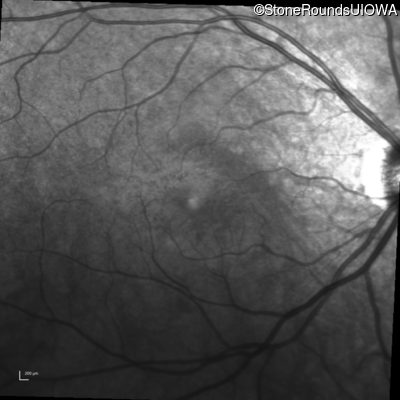

Infrared Fundus Photograph - Right - 20/40 +1

Exemplar

Infrared Fundus Photograph - Left - 20/50